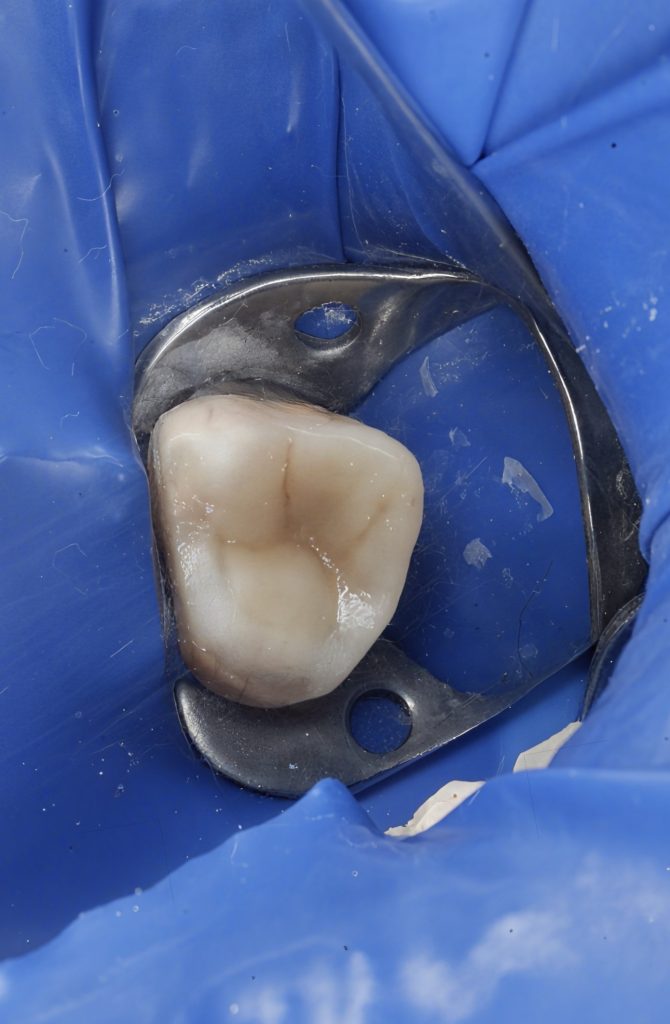

1. Isolation and Access

Rubber dam isolation was established to maintain asepsis. Under DOM, caries excavation and refinement of the access cavity were performed, preserving pericervical dentin.

3. Deep Marginal Elevation (DME)

Subgingival margins on the proximal surface were managed using DME:

- Matrix Placement: A sectional matrix was positioned, stabilized by a separating ring, followed by a secondary “matrix within matrix” adaptation for precise control of the deep cervical margin.

- Adhesive Protocol: Selective enamel etch, followed by universal adhesive application under magnification.

- Incremental Elevation: Flowable composite was layered to elevate the margin to a supragingival, cleansable, and sealable level. This allowed ideal conditions for subsequent adhesive procedures.